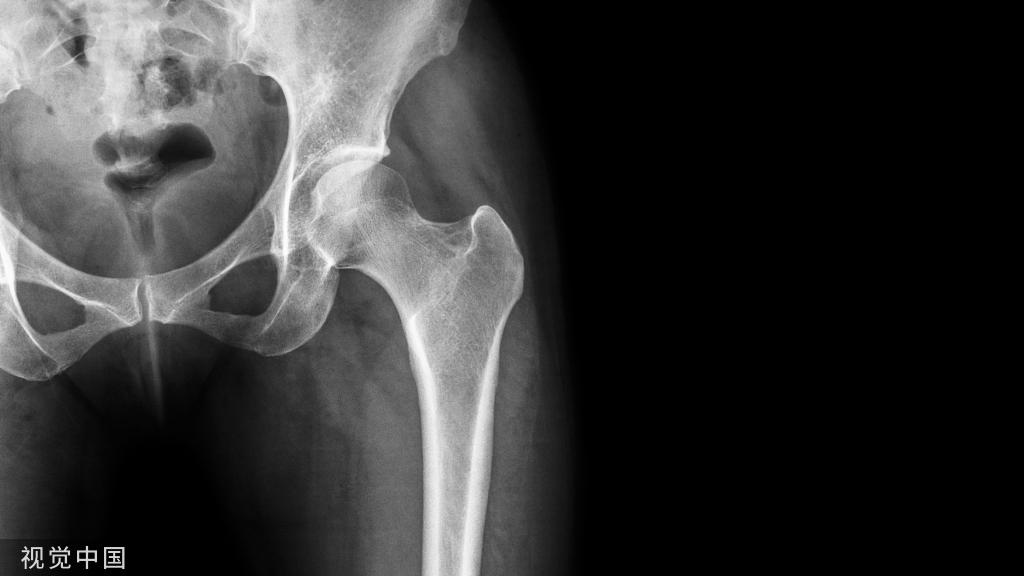

软骨发育不全患者可见典型的椎小关节狭窄、椎弓根短小和骨性椎管狭窄,其椎体后缘压迹为继发于椎管狭窄的代偿性改变。

病例 2,2 岁男孩,软骨发育不全。腰椎侧位片可见椎体呈子弹形(黑箭),另外还可以见到椎体后缘扇贝样凹陷,正位片课件典型的腰椎弓根间距逐渐缩小(红线)。